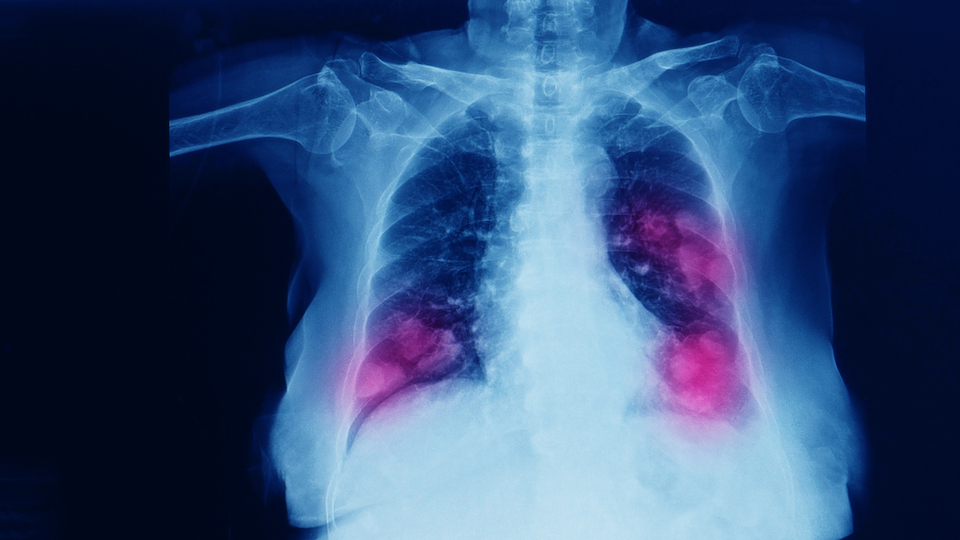

Göğüs Cerrahisi Uzmanı Prof. Dr. Bülent Arman, "Akciğer, etrafı damarlarla çevrili, hava kesecikleri ve bu keseciklere hava taşıyan hava yollarından oluşan bir organ. Bu özellikleriyle oksijeni alıp damarlara ulaştırıyor, damarlardan aldığı zararlı karbondioksiti havaya bırakmayı ve böylece yaşamın devam etmesini sağlıyor. Ancak bazı kişilerde KOAH ya da kronik bronşit gibi nedenlerle akciğer görevini tam olarak yapamıyor. Burada da devreye bazı tedavi yöntemleri giriyor" diye konuştu.

Akciğer temizliğinin hastanın ön tetkikleri yapıldıktan sonra genel anestezi altında yapıldığını ifade eden Prof. Dr. Arman, “Bronkoskopi adı verilen ince ve ışık kaynaklı, aynı zamanda video kameraya bağlı bir sistem ile anestezi tüpü içerisinden akciğer kanallarına ulaşılır. Öncelikle tüm ulaşılabilen hava yolları (bronşlar) gözlemlenir. Yollar içindeki iltihap ve fazla balgamlar aspire edilir. Hava yolları genişleten ilaçlar ve serum ile hava yolları yıkanır ki buna akciğer lavajı denilir. Anestezi aygıtı yardımı ile hava yolları içine pozitif oksijenli hava vererek hava yolları ve kapalı hava kesecekleri açılır ve daha fazla oksijenin kan dolaşımına katkısı sağlanır" dedi.

Akciğer temizliğiyle birlikte biyopsinin de yapıldığına değinen Prof. Dr. Arman, “Böylece hiç akılda yokken erken bir akciğer kanseri yakalanmış (röntgende de belirti yokken) ve erken teşhis konmuş olur. Netice olarak akciğer temizliği ile kronik akciğer hastalarının nefes darlıkları azalır, yaşam kalitesi artar. İlave hastalıklar daha etkili tedavi edilir ve erken kanser teşhisi yapılmış olur" diye konuştu.